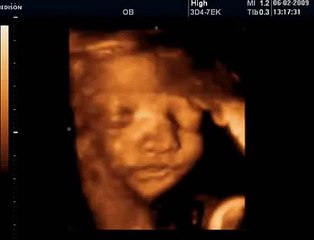

HAFTA HAFTA Gebelik Takibi deneyimli kadın doğum uzmanı Op. Dr. Fatih Esen'in videolu anlatımıyla Bebek.Tv'de: br br br 31 Haftalık Gebelik: br br Deneyimli kadın doğum uzmanı Op. Dr. Fatih Esen anne-baba adaylarına gebeliğin 31. haftasında anne adayı ve bebekte neler yaşandığını anlatıyor, önemli hatırlatma ve tavsiyelerde bulunuyor. br br Bu video Hafta Hafta Gebelik kanalı kapsamında Bebek.Tv tarafından hazırlanmıştır. br br Gebelik-doğum-bebek gelişimi videoları Bebek.Tv'de: br Bebek videoları: br Hamilelikte beslenme: br Kaç haftalık hamileyim, kaç aylık hamileyim? br Hamilelikte öksürük bebeğe zarar verir mi? br br Bebek.